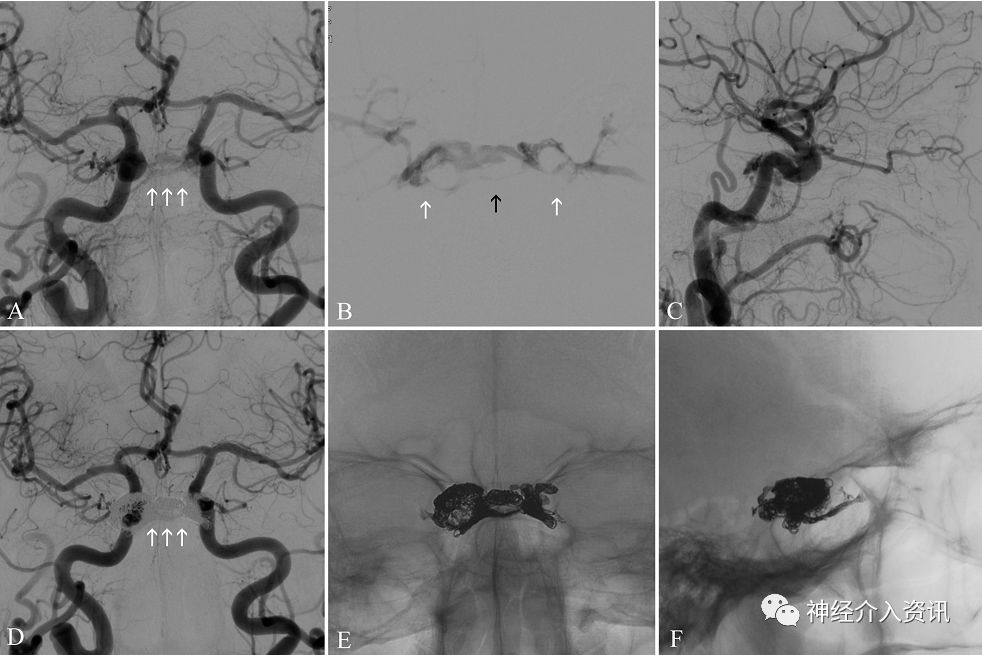

图2

图一病例操作细节;

(A) X-ray,正位,显示仅有弹簧圈最终铸型;

(B) 右侧颈总动脉DSA,正位,动脉晚期,显示左侧海绵窦早显,表明硬脑膜颈内动脉海绵窦瘘(DCCF)(白色箭头)部分闭塞;

(C, D, E) 路图、正位,演示经放置在左侧海绵窦的Echelon导管注入的连续步骤。Onyx注射剂充满了右侧海绵窦腔(C)、另侧海绵间窦(D)和左侧海绵窦(E);X-ray,正位,显示弹簧圈和Onyx(Medtronic)组成的最终铸型。